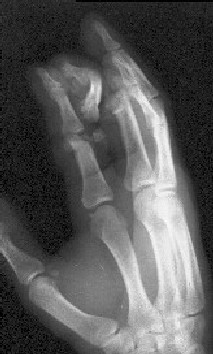

Уважаемые коллеги, в травмотделение БСМП Ангарска поступил пациент с отрывом 3 пальца на уровне проксимального межфалангового сустава (дистальная

часть пальца висит на кожном лоскуте с латеральной стороны пальца шириной 1 см, повреждены сухожилия сгибателей и разгибателей), многооскольчатым переломом головки основной фаланги 2 пальца, рваной раной в проекции сустава, превышающей половину диаметра пальца (сухожилия целы)(снимок 1, снимок 2). Выполнена ПХО ран, МОС спицами трансартикулярно (снимок 3, снимок 4). При обсуждении тактики лечения возникли разногласия между врачом, выполнявшим ПХО, и заведующим. Зав. отделением считает, что выбранная тактика неверна, и необходимо было после проведения ПХО сделать вытяжение типа Черкес-Заде за пальцы. Просим высказать присутствующих свое мнение о выполненной операции и о дальнейшей тактике лечение больного. Заранее спасибо.